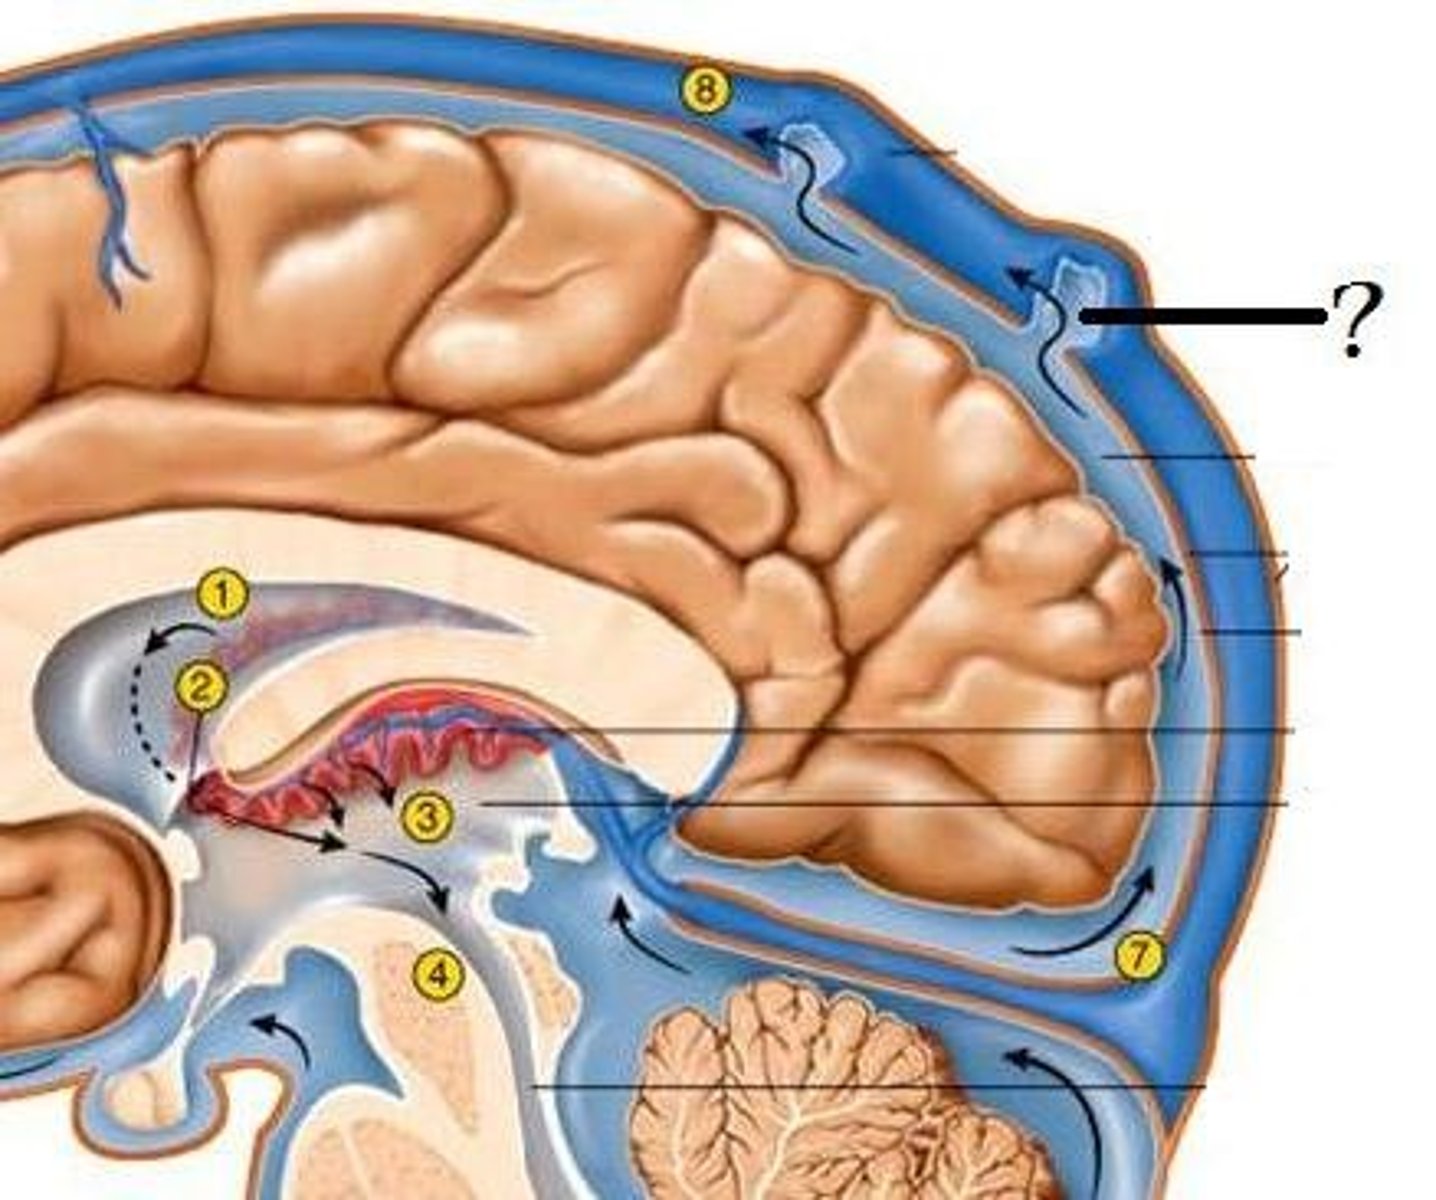

arachnoid villus

superior sagittal sinus

choroid plexus (of ventricles)

lateral ventricles

fourth ventricle

third ventricle

cerebral aqueduct (brainstem)